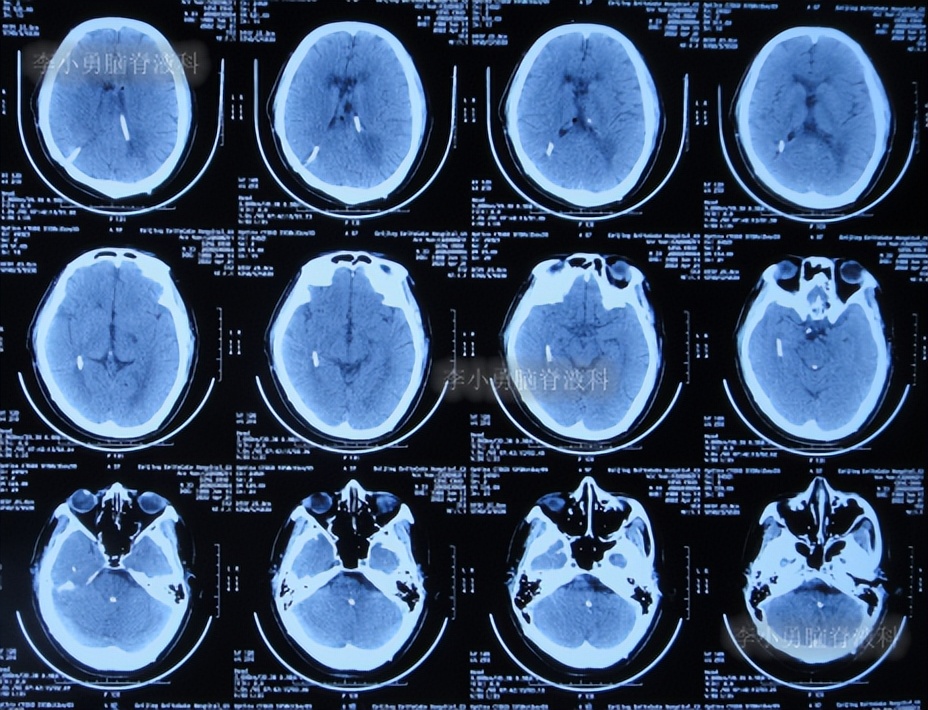

二、第1次在李小勇脑脊液科治疗过程和结果

2020年6月4日(脑囊虫切除术+第三脑室造瘘术后2年5个月,2次脑室腹腔分流术均堵管,期间历经5次住院但脑积水仍反复复发)住入李小勇脑脊液科,入院时:神志朦胧,饮食差,问答有误,自己站立不稳,双眼对视(图-19);既往史:口服抗癫痫药物,青霉素过敏。头颅CT示鞍上占位术后,脑室内可见引流管,脑室系统扩张(图-20)。

图-20:2020年6月4日头颅CT

入院后2天即2020年6月6日,进行了脑室腹腔分流管拔除术+脑室穿刺外引流术(图-21)。

图-21:2020年6月6日头颅CT

2020年6月8日(住院治疗4天),查头颅CT示脑室有所缩小,有少量积血(图-22),引流管培养出表皮葡萄球菌感染。

图-22:2020年6月8日头颅CT

2020年6月10日(住院治疗6天),查头颅CT示脑室缩小(图-23)。

图-23:2020年6月10日头颅CT